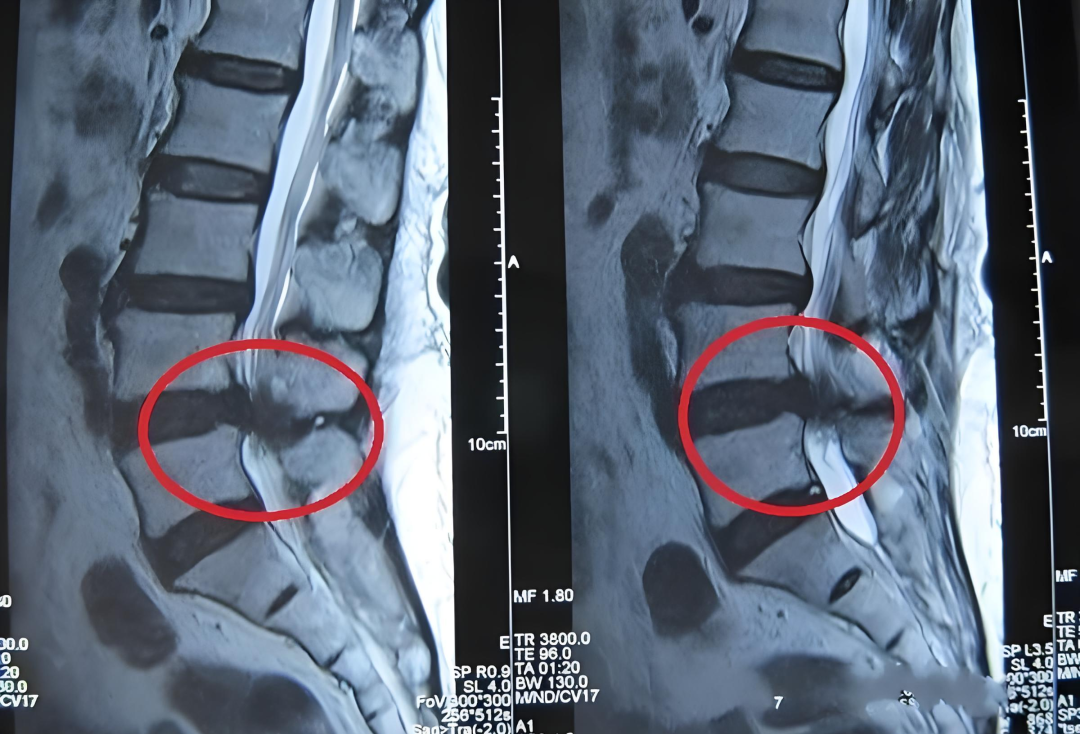

首先,我们要清楚,腰椎间盘突出是椎间盘外侧的纤维环破裂,导致内部的髓核组织向后方突出,进入椎管空间的现象。

但单纯的突出未必会产生症状。只有当突出的部分挤压或刺激到神经根,并且神经根受到的压力较大、没有足够空间躲避时,才会出现疼痛、麻木等神经症状。所以本质上,腰椎间盘突出症是一种神经受压迫引发的综合征,其典型症状往往体现在下肢。